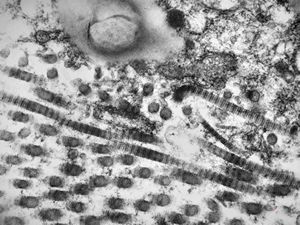

M, 43y. | myeloid leukemia … Auer bodies